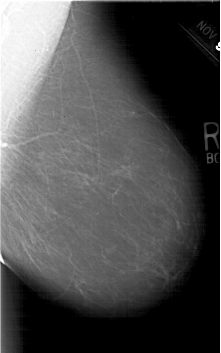

A_1644_1.RIGHT_MLO

RIGHT_CC LINES 6196 PIXELS_PER_LINE 4096 BITS_PER_PIXEL 12 RESOLUTION 43.5 NON_OVERLAY

RIGHT_MLO LINES 6346 PIXELS_PER_LINE 3961 BITS_PER_PIXEL 12 RESOLUTION 43.5 NON_OVERLAY